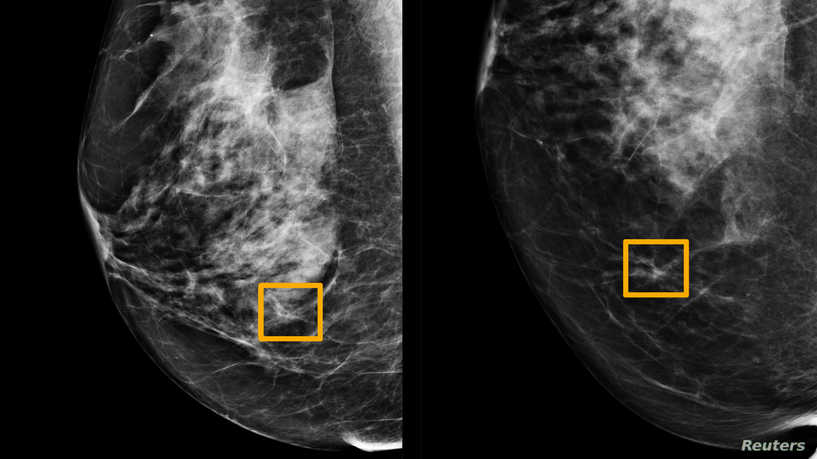

芝加哥-美国和英国的研究人员报道,谷歌人工智能系统被证明与放射线专家一样擅长通过筛查乳房X线照片来检测哪些女性患有乳腺癌,并显示出减少错误的前景。

然后,他们将系统的性能与英国的25856张乳房X线照片和美国的3097张乳房X线照片的实际结果进行了比较。

这项研究表明,人工智能系统可以以与放射专家相类似的准确度来识别癌症,而在美国的小组中,假阳性结果的数量减少了5.7%,在英国的小组中,减少了1.2%。

它还将错误分类为正常的误报阴性的数量减少了,美国组减少了9.4%,英国组减少了2.7%。